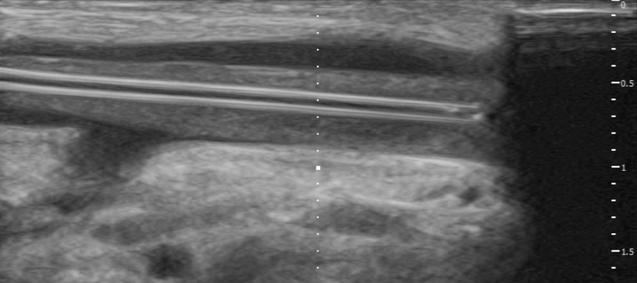

Nie tylko w zaawansowanych procedurach można wykorzystać technologie immersyjne. W zakresie kaniulacjii pod kontrolą ulstrasonograficzną Nguyen T, Plishker W et. al. wykazali, że eliminując konieczność naprzemiennego obserwowania pacjenta oraz obrazów ultrasonograficznych wyświetlanych na oddzielnym monitorze, czas wykonania procedur u nowicjuszy poprawił się o 17%, natomiast u ekspertów czas ten skrócił się o 5%. Dowodzi to tym samym, że AR poprawia komfort i upraszcza koordynację wzrokoworuchową [15].

Doświadczenia własne w tym zakresie wskazują również na korzyści wynikające z lepszej ergonomii stanowiska i oszczędności miejsca gdzie w ciasnych pomieszczeniach takich jak sale chorych, tradycyjny ekran USG może być trudy do ustawienia. Ponadto Headsety AR umożliwiają wyświetlanie obrazu ultrasonograficznego w polu widzenia operatora, eliminując konieczność korzystania z dodatkowego monitora [ryc 6] Wykorzystanie headsetu AR eliminuje również konieczność dotykania dodatkowych urządzeń, takich jak ekran USG czy klawiatura co w przypadku procedur aseptycznych pozwala operatorowi korygować ustawienia urządzenia zachowując jednocześnie pełną jałowość. Możliwość sterowania interfejsem gestami lub komendami głosowymi dodatkowo poprawia precyzję i bezpieczeństwo procedury.

Rycina6.ProcedurakaniulacjizwykorzystaniemARHoloLens2,nałożeniem obrazuultrasonograficznegotuzprzedobiektem